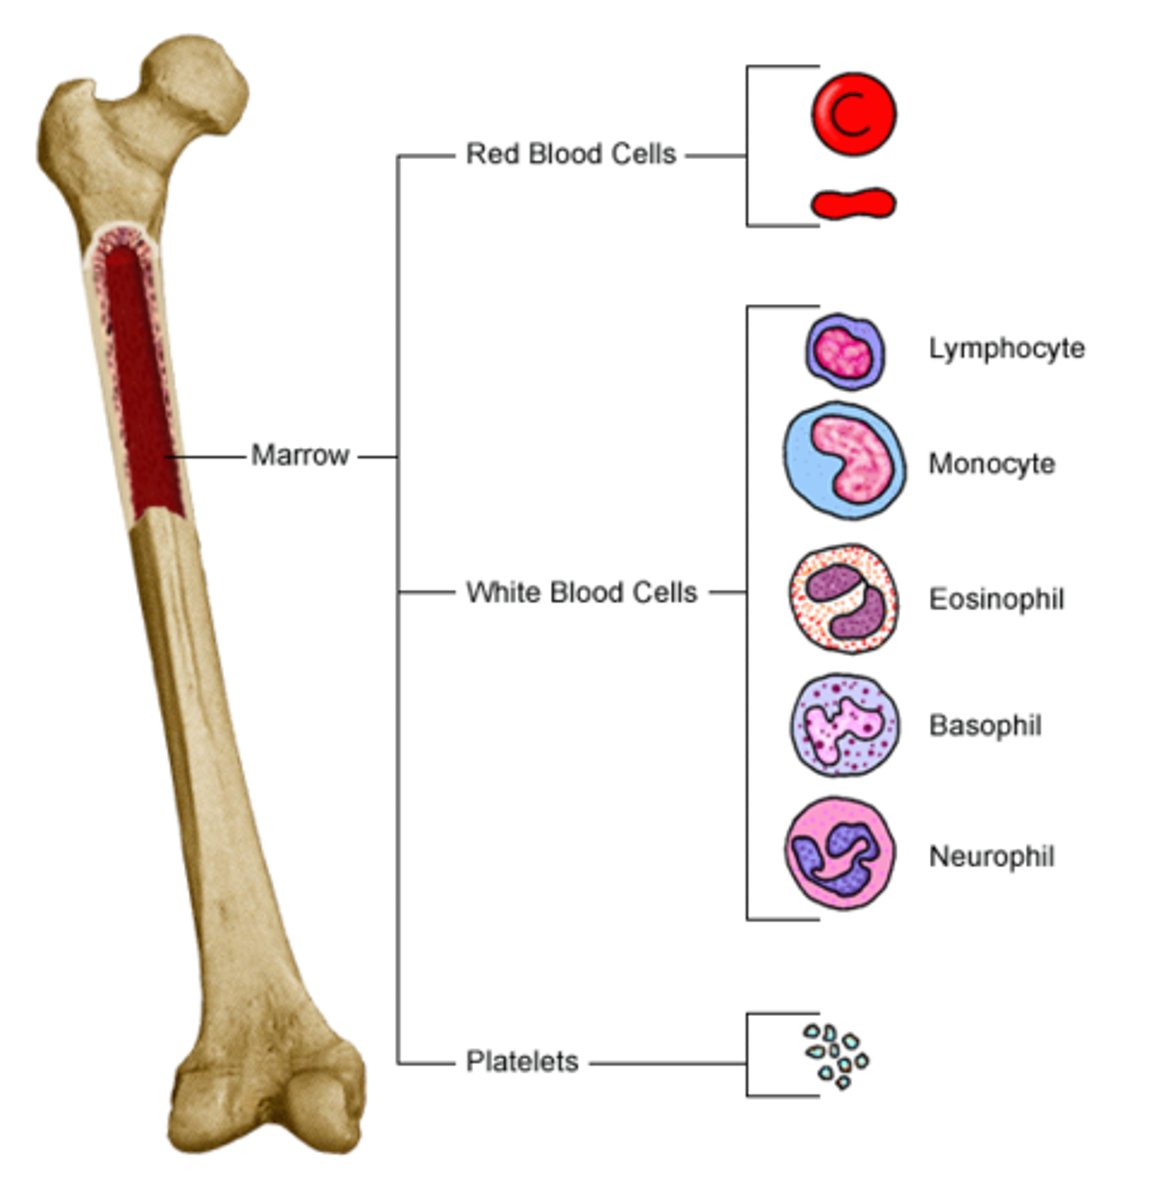

Hematopoiesis

The formation of blood cells from stem cells in the bone marrow

Myeloid stem cell

Differentiates into erythrocytes/platelets, and granulocytes/monocytes

Leukocytes

White blood cells

Granular leukocytes

Neutrophils, eosinophils, basophils

PHILLED (filled) with granules (enzymes)

Agranular leukocytes

Lymphocytes and monocytes

No granules

Neutrophils

Structure: Nuclei has three or more lobes, granules stain light pink

Function: The most common WBC; fights bacterial infections by engulfing bacteria by phagocytosis

Eosiniphils

Structure: Nuclei has two lobes, granules stain bright red

Function: A WBC that digests and destroys parasitic worms, they also play a role in allergy and immune response

Basophils

Structure: Nuclei is U or S shaped but is obstructed by HUGE blue granules

Function: A WBC that produces histamine --> causing inflammation during an immune response

Monocytes

Structure: Largest WBCs, U shaped nucleus

Function: A large WBC that transform into macrophages to fight off viruses and chronic infections

Lymphocytes

Structure: Has a large, dark purple nucleus that takes up most of the cell volume

Function: B cells make antibodies, T cells fight off viral infections, NK cells